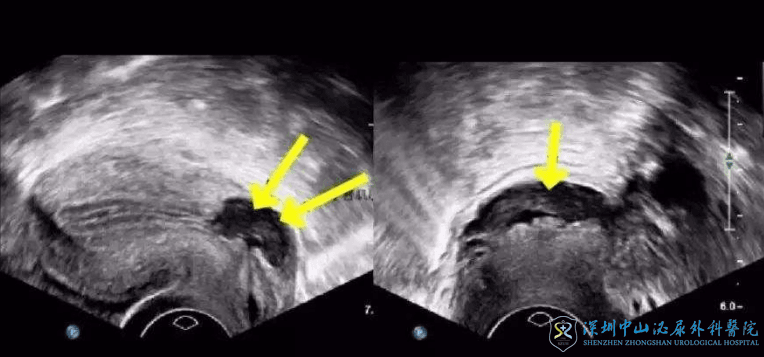

子宫切口憩室,又称子宫切口疤痕缺损,指的就是剖宫产后,子宫没有正常愈合,在切口的地方出现了肌层缺损、变薄,从而凹陷,形成一个小洞洞、小窝窝。

月经来后,小洞洞里会留有月经血和内膜,当行经结束,患者会出现血淋漓、经期延长的现象,可能还伴有腹痛。